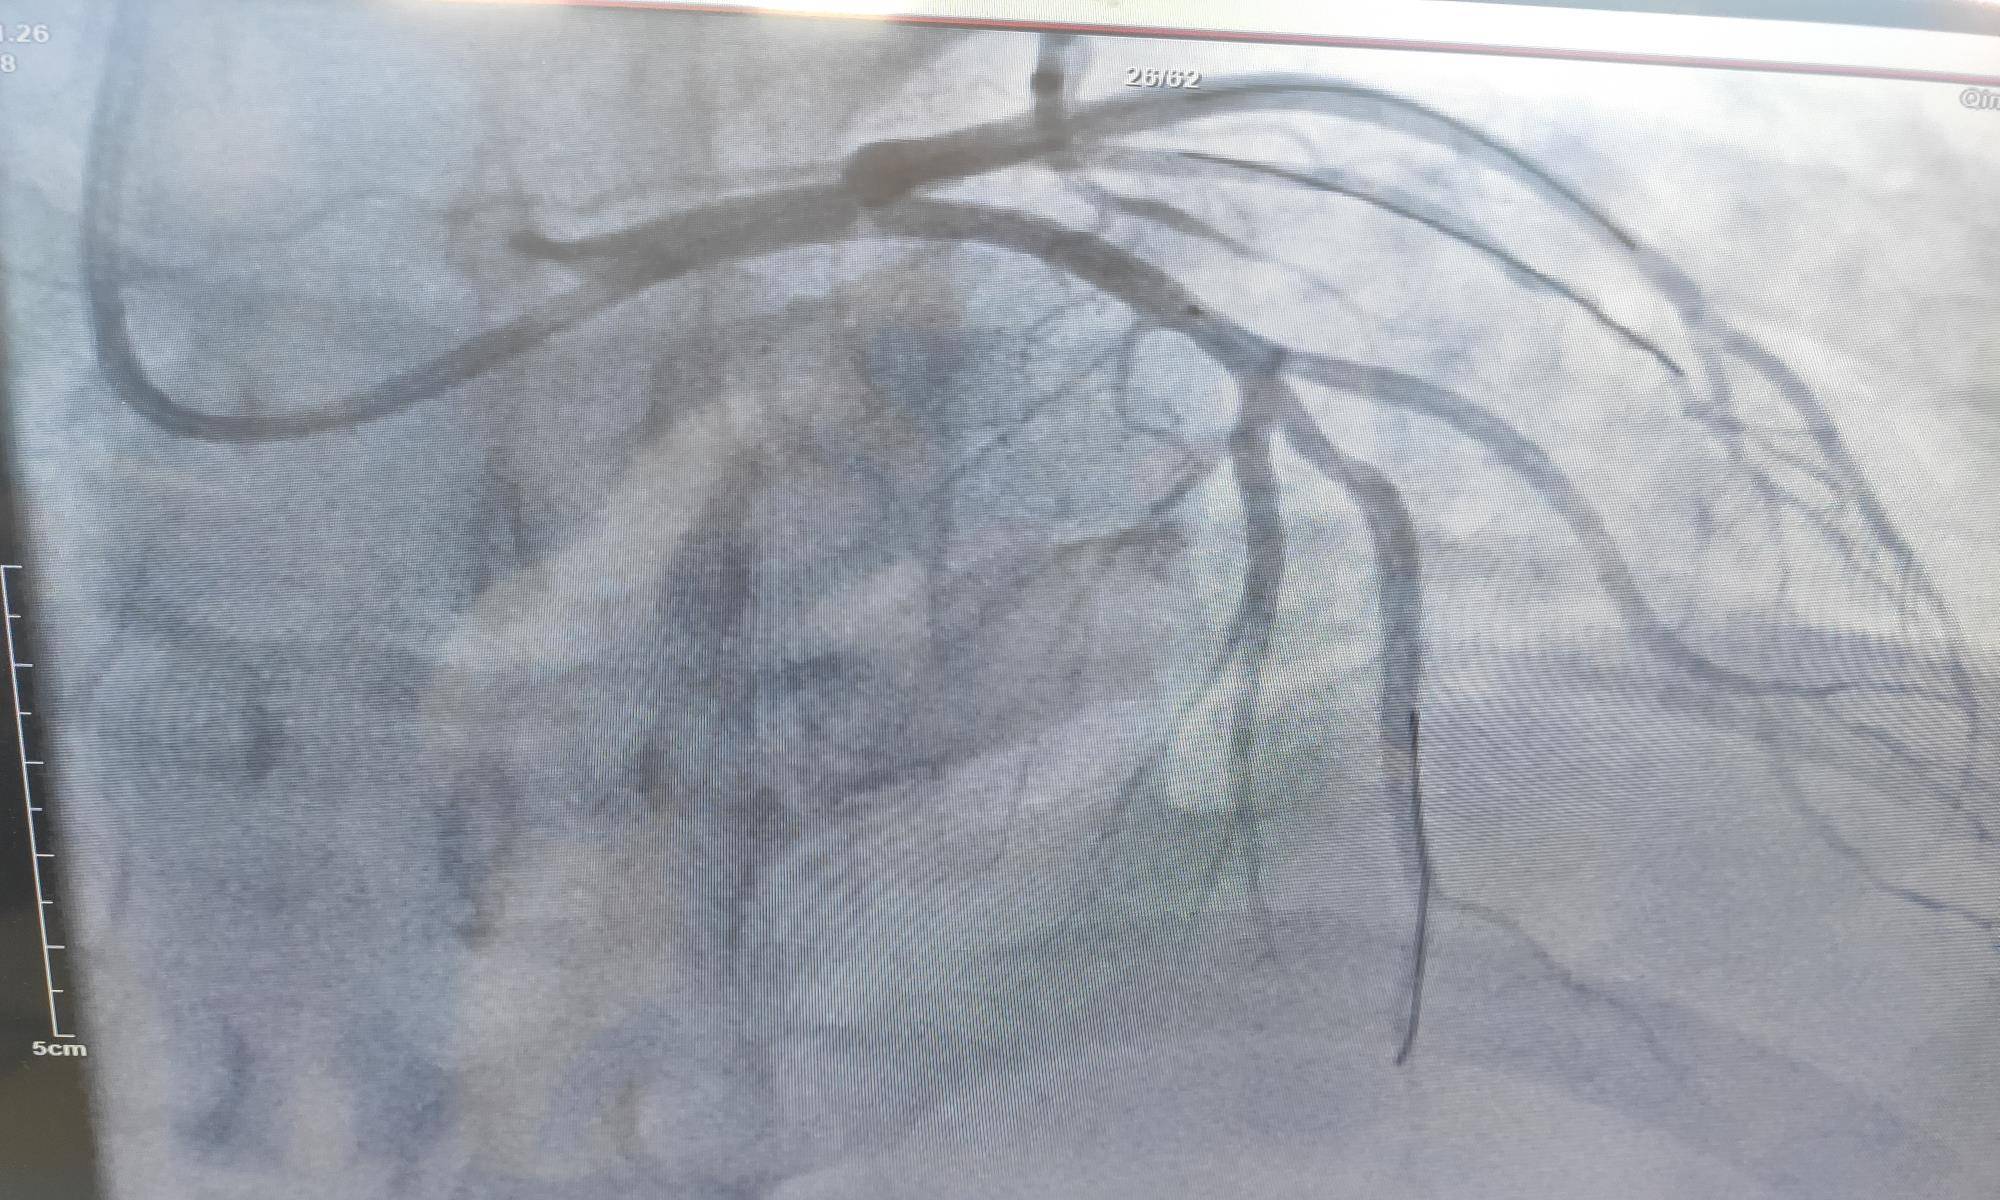

造影结果显示:左主干通畅 , 前降支开口100%闭塞 , 可见回旋支向前降支远段发出侧支循环 。 右冠近段、远段斑块 。 可见右冠向前降支发出侧支循环 。 最终在前降支出放了1枚支架 。